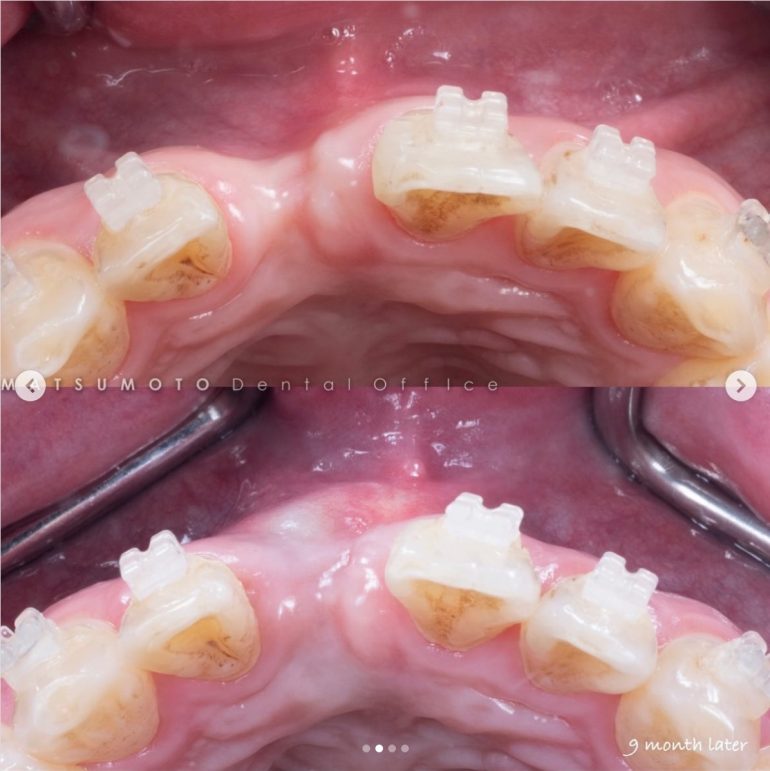

術前写真

上顎:インプラントが不適切な位置に入っており、仮歯を無理やり入れている状態。

下顎:インプラント周囲の骨がなくなっており、保村不可能な状態。

パノラマX線

上顎:インプラントは保存できる状態。

下顎:インプラントを含め全て保存不可能な状態。

All-on-6を終えて

最終補綴

上顎:ロケーターアバットによる義歯

下顎:フルジルコニアブリッジ

治療のリスクと副作用

治療期間:約半年

治療費:¥3,850,000(税込)

リスク:インプラントのネジが緩むことはありますが、なるべく連結しないような設計にしているので、問題をはやく見つけやすくしております。